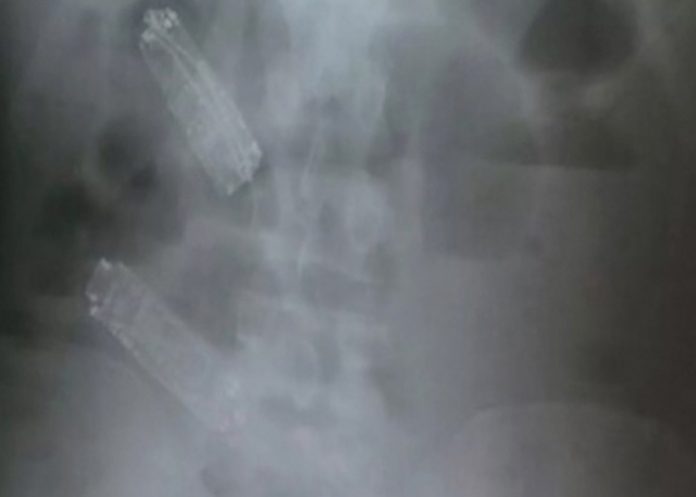

Después de someterlo a un examen de rayos X en el que se constató que tenía los tres aparatos en su estómago, los médicos le recetaron laxantes y lo devolvieron a prisión.

Sin embargo, no logró expulsarlos y fue conducido a un hospital para ser sometido a una operación que se fijó para ayer jueves y que no pudo realizarse porque el recluso murió unas horas antes.